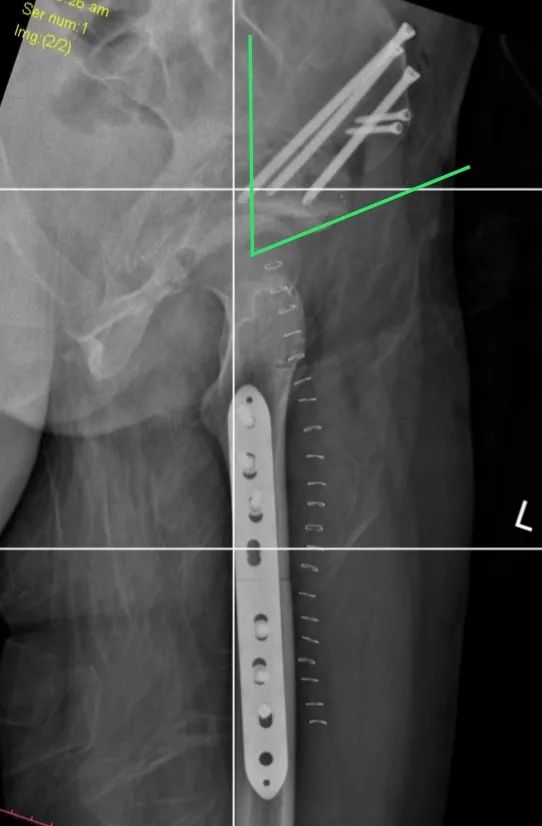

手術(shù)取得圓滿成功,術(shù)后恢復(fù)良好。

術(shù)后